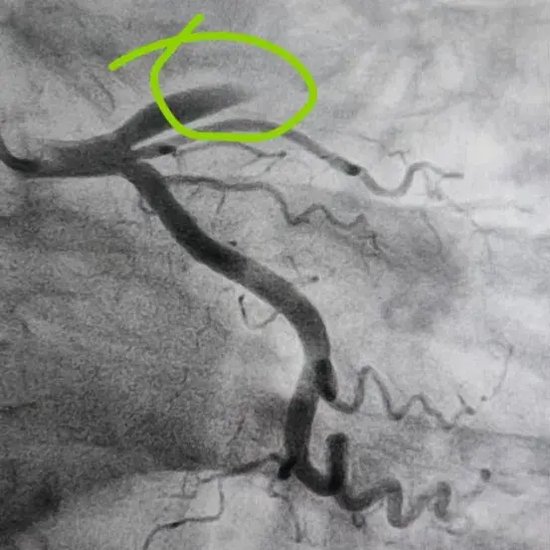

术前患者前降支血管完全闭塞

患者术前前降支闭塞